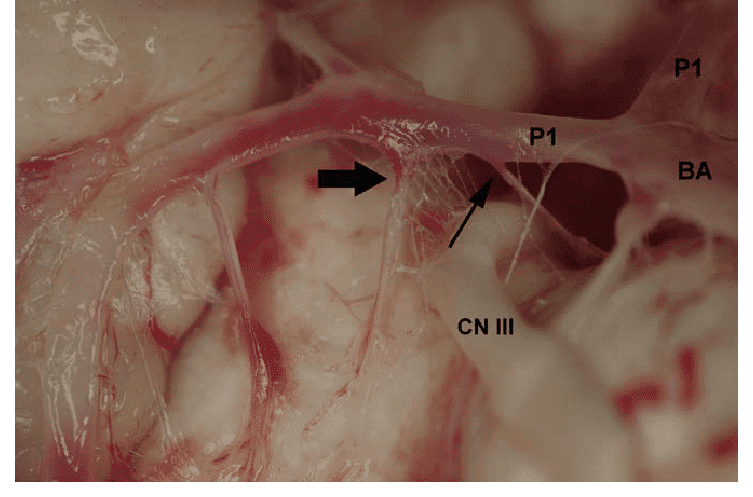

Paresia de oculomotor aguda por oclusão isolada de P1 revertida com trombectomia